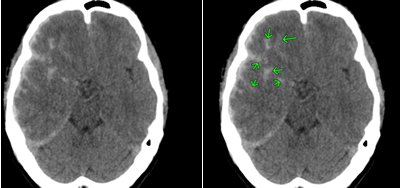

左顔面部を強打した脳挫傷の事例

CT画像では、中央部右側に白い○状の形があるのが読み取れます。これが脳挫傷が生じた部分です。

これは、バイクを運転していたところ、自動車と出合い頭で衝突した被害者のものです。左顔面部を強打し、左下顎骨骨折、左頬骨骨折となり、左下からの突き上げる衝撃で、左側頭葉に局在性の脳挫傷が発症したものです。

左側頭部を強打した脳挫傷の事例

CTの3D画像では骨折線が確認できます。CT画像では矢印のところに異常があります。

自転車に乗っていたところ、軽自動車と出合い頭で衝突した被害者のものです。左側頭部を骨折し、その衝撃により、打撲部位の直下の脳組織が挫滅となりました。これも、局在性の脳挫傷です。